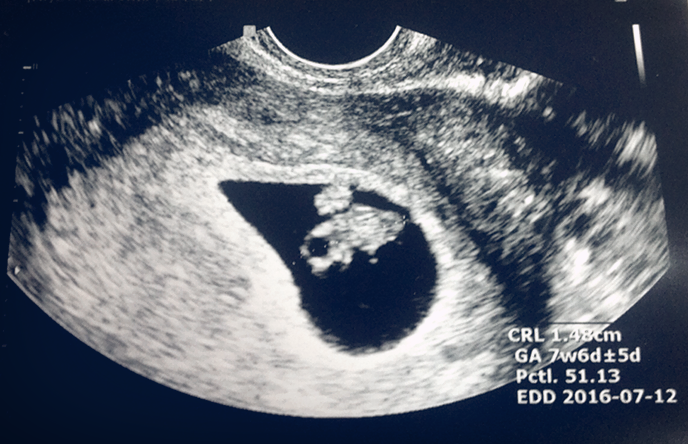

현실은 보통 이렇다. 입덧은 임신을 알게 되는 순간부터 시작된다. 임신의 인지 자체가 입덧에 큰 영향을 준다는 건 나도 처음 알았다. 경험 있는 친구들이 말하길, 임신의 여러 증상은 임신 확인 후 더 분명히 나타난다고 한다. 그렇다면 입덧은 신체보다는 정신의 문제인 것 같았다. 몸의 변화는 나도 어쩔 수 없지만 정신의 영향이라면 내가 어느 정도 조절할 수 있지 않을까? 이런 생각을 할 무렵, 어느 날 친구에게서 메시지가 왔다.

새봄이의 아기공룡 시절